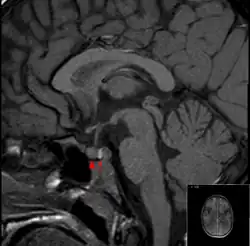

An die körperliche Untersuchung schließen sich Hormonmessungen und Funktionstests an. Bei klinischem Verdacht sollten Hormonuntersuchungen bei einem Endokrinologen vor bildgebenden Verfahren durchgeführt werden, da die bildgebenden Verfahren häufig falsch positive Befunde ergeben („Incidentalome“). Als bildgebende Verfahren finden die Röntgenaufnahme der Sella turcica im Seitbild des knöchernen Schädels, die Computertomografie, die Magnetresonanztomografie und die Somatostatin-Rezeptor-Szintigrafie Anwendung.